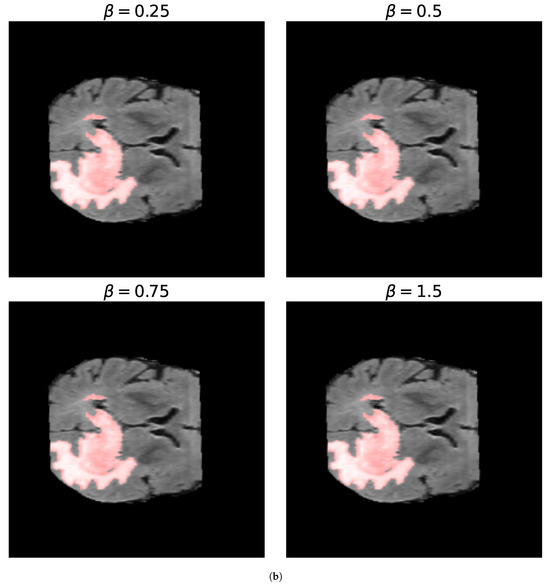

4.3. Optimization Metrics for Biomedical Image Segmentation